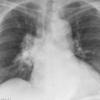

Radiation case 2

Date: 02/10/2005

Views: 3258